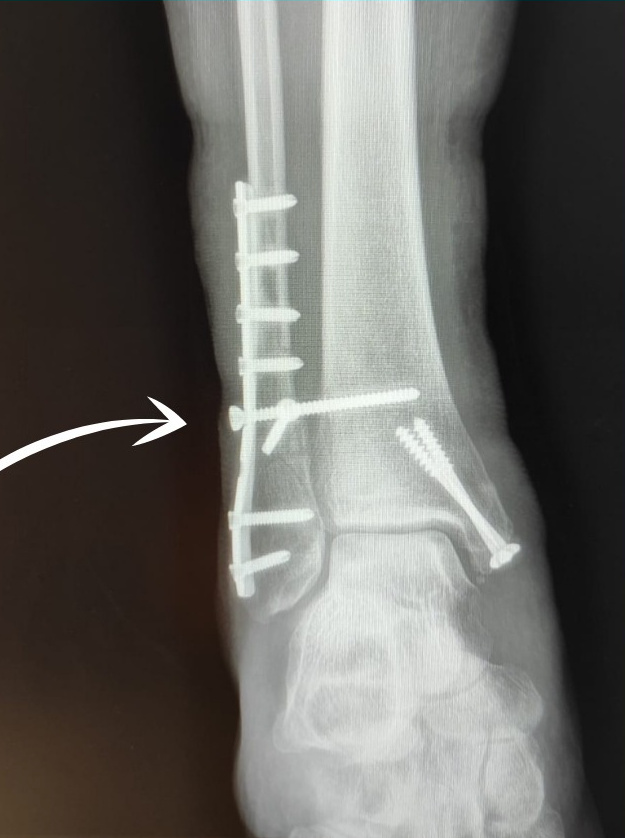

В условиях отделения возможен широкий спектр оказания экстренной травматологической и плановой ортопедической помощи с выполнением всевозможных манипуляций для достижения максимального результата - выздоровления пациента.

В лечении врачи придерживаются соблюдения клинических стандартов лечения, разработанных Минздравом РФ, в том числе с использованием передовых высокотехнологичных методов.

репозиция переломов